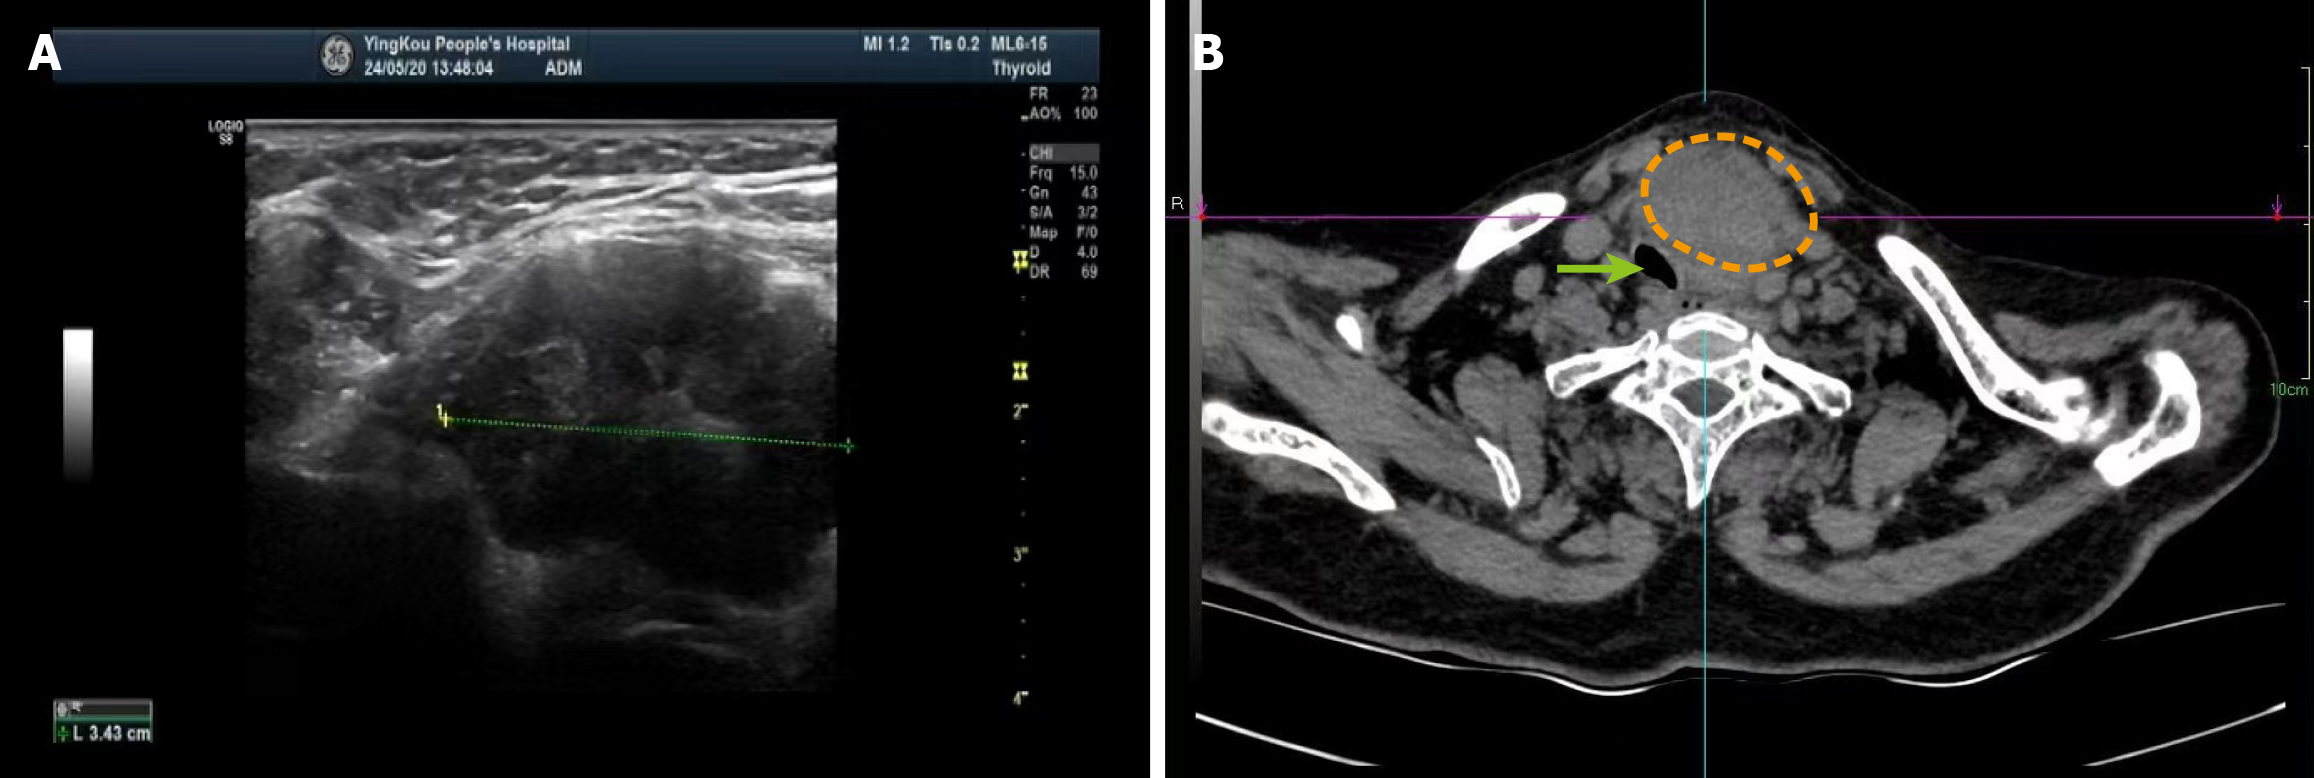

Figure 4 Imaging examinations.

A: Thyroid ultrasonography showing a mass with regular morphology and well-defined margins, closely associated with the lower pole of the thyroid gland; B: Contrast-enhanced axial computed tomography scan of the neck demonstrating a large mass causing tracheal deviation. The orange dotted line outlines the approximate tumor extent, and the green arrow indicates the deviated trachea.